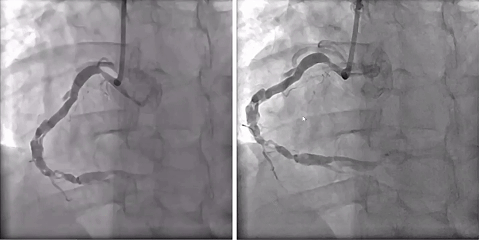

入院造影

冠状动脉造影显示,左冠脉整体状况尚可;右冠脉呈弥漫性严重病变,病变核心位于第二转折区,表现为典型血管编织样改变及多腔结构(至少两个假腔)。具体受累范围包括:(1)中远段弥漫性扩张伴血管分层;(2)第二转折后严重狭窄及继发的狭窄后扩张(累及PLA);(3)PDA全程弥漫性重度狭窄。结合患者症状持续+狭窄严重+真腔存在连通可能,决定再次行介入治疗。

左冠造影

右冠造影